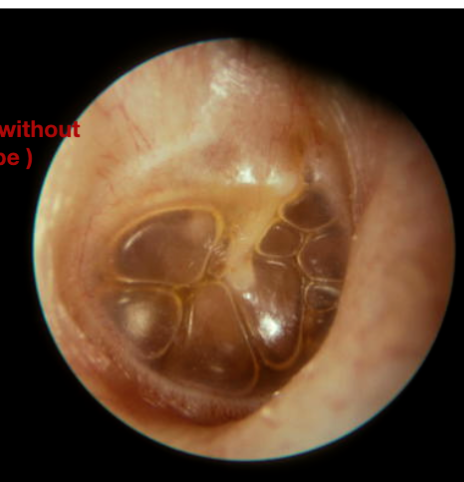

Effusion

- Answer: Serous Otitis Media (Otitis Media with Effusion)

- A- What is the treatment?

- If its bilateral observations for 3 month, if its unilateral observations for 6 mont, usually no need for treatment but if the pt complete the period without improvement we do (myringotomy + aspiration + ventilation tube)

- B- What will be the result of tympanogram?

- Type B

Congenital Cholesteatoma

- Question: 7 years old with hearing loss. No history or ear discharge or infection.

- Answer:

- A- What is the diagnosis?

- Congenital cholesteatoma

- B- What is the treatment?

- Reconstructive surgery and mastoidectomy